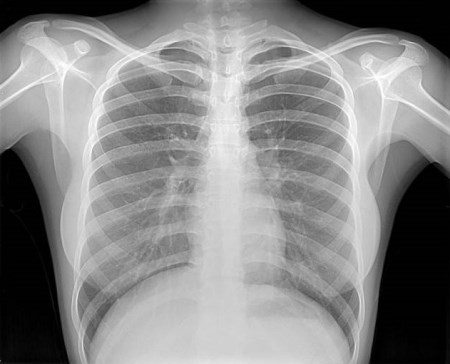

Рентгенография грудины (со снимком)

Рентгенография грудной клетки - это метод диагностики, позволяющий получить изображение органов грудной полости с помощью облучения рентгеновыми лучами.

Различные ткани организма в зависимости от своей плотности по-разному пропускают рентгеновы лучи, а значит, по-разному отображаются на снимке (рентгенограмме).

Рентген грудной клетки дает возможность изучить костные структуры (ребра, грудину, позвоночник), легкие, плевру, бронхи и трахею, сердце и средостение, а также оценить состояние мягких тканей этой области.